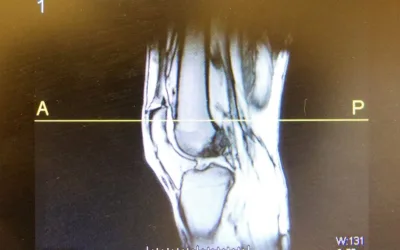

ACL Reconstruction Rehab – Week-by-Week Recovery Guide with Praxis Physio

ACL reconstruction is just the beginning. At Praxis Physiotherapy in Brisbane, our expert-led, week-by-week rehab plan takes you from prehab to full return-to-sport. Learn how our proven approach, trusted by elite Brisbane teams and surgeons, helps you recover stronger and smarter.